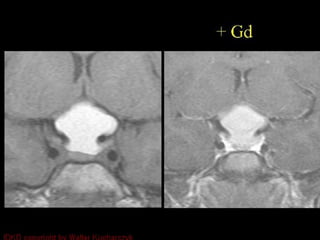

Rathke cleft cyst

• Very common and very few are symptomatic

• Importation to not over treat them